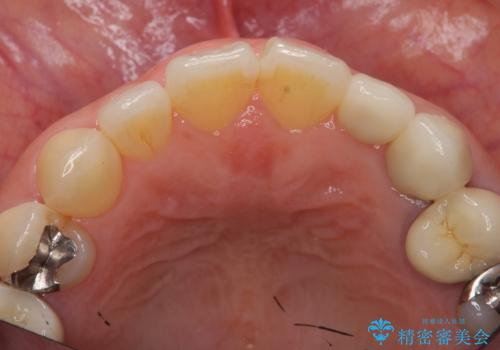

小さい前歯は、反対側と合わせた形にしました。

- 25万円 内訳 左上23:ジルコニアクラウン(スペシャル)各10万円、仮歯 各1万円、オフィスホワイトニング(エクセレント)3万円費用は治療当時の料金となります

左右対称に仕上げることができ、治療には非常に満足していただきました。